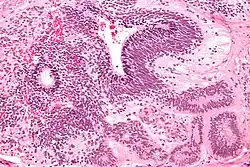

Micrograph of the primitive neuroepithelium of an immature teratoma. H&E stain.

An immature teratoma contains varying compositions of adult and embryonic tissue. The most common embryonic component identified in immature teratomas is the neuroectoderm.[19] Occasionally, tumors may present neuroepithelium that resemble neuroblasts.[19] Tumors may also present embryonic components such as immature cartilage and skeletal muscle of mesodermal origin.[19] Immature teratomas composed of embryonic endodermal derivatives are rare.[19]

Often a mature cystic teratoma is misdiagnosed as its immature counterpart due to the misinterpretation of mature neural tissue as immature.[20] While mature neural cells have nuclei with uniformly dense chromatin and neither exhibit apoptotic or mitotic activity, immature neural cells have nuclei with vesicular chromatin and exhibit both apoptotic and mitotic activity.[20] A recent study has identified the use of Oct-4 as a reliable biomarker for the diagnosis of highly malignant cases of immature teratomas.[21]